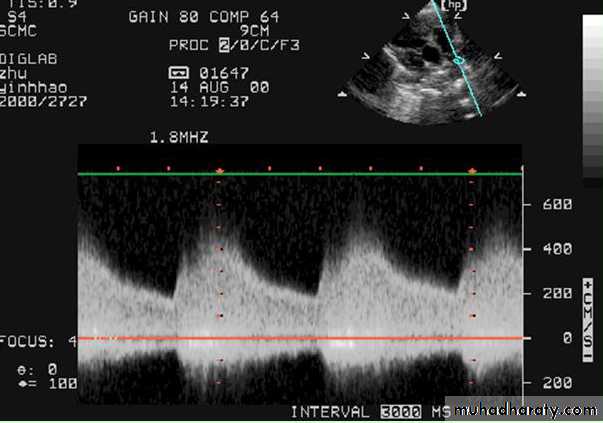

PATENT DUCTUS ARTERIOSUS (cont.)

Echo: is diagnostic2D echocardiogram can idendtify the PDA which can be confirmed by Doppler.